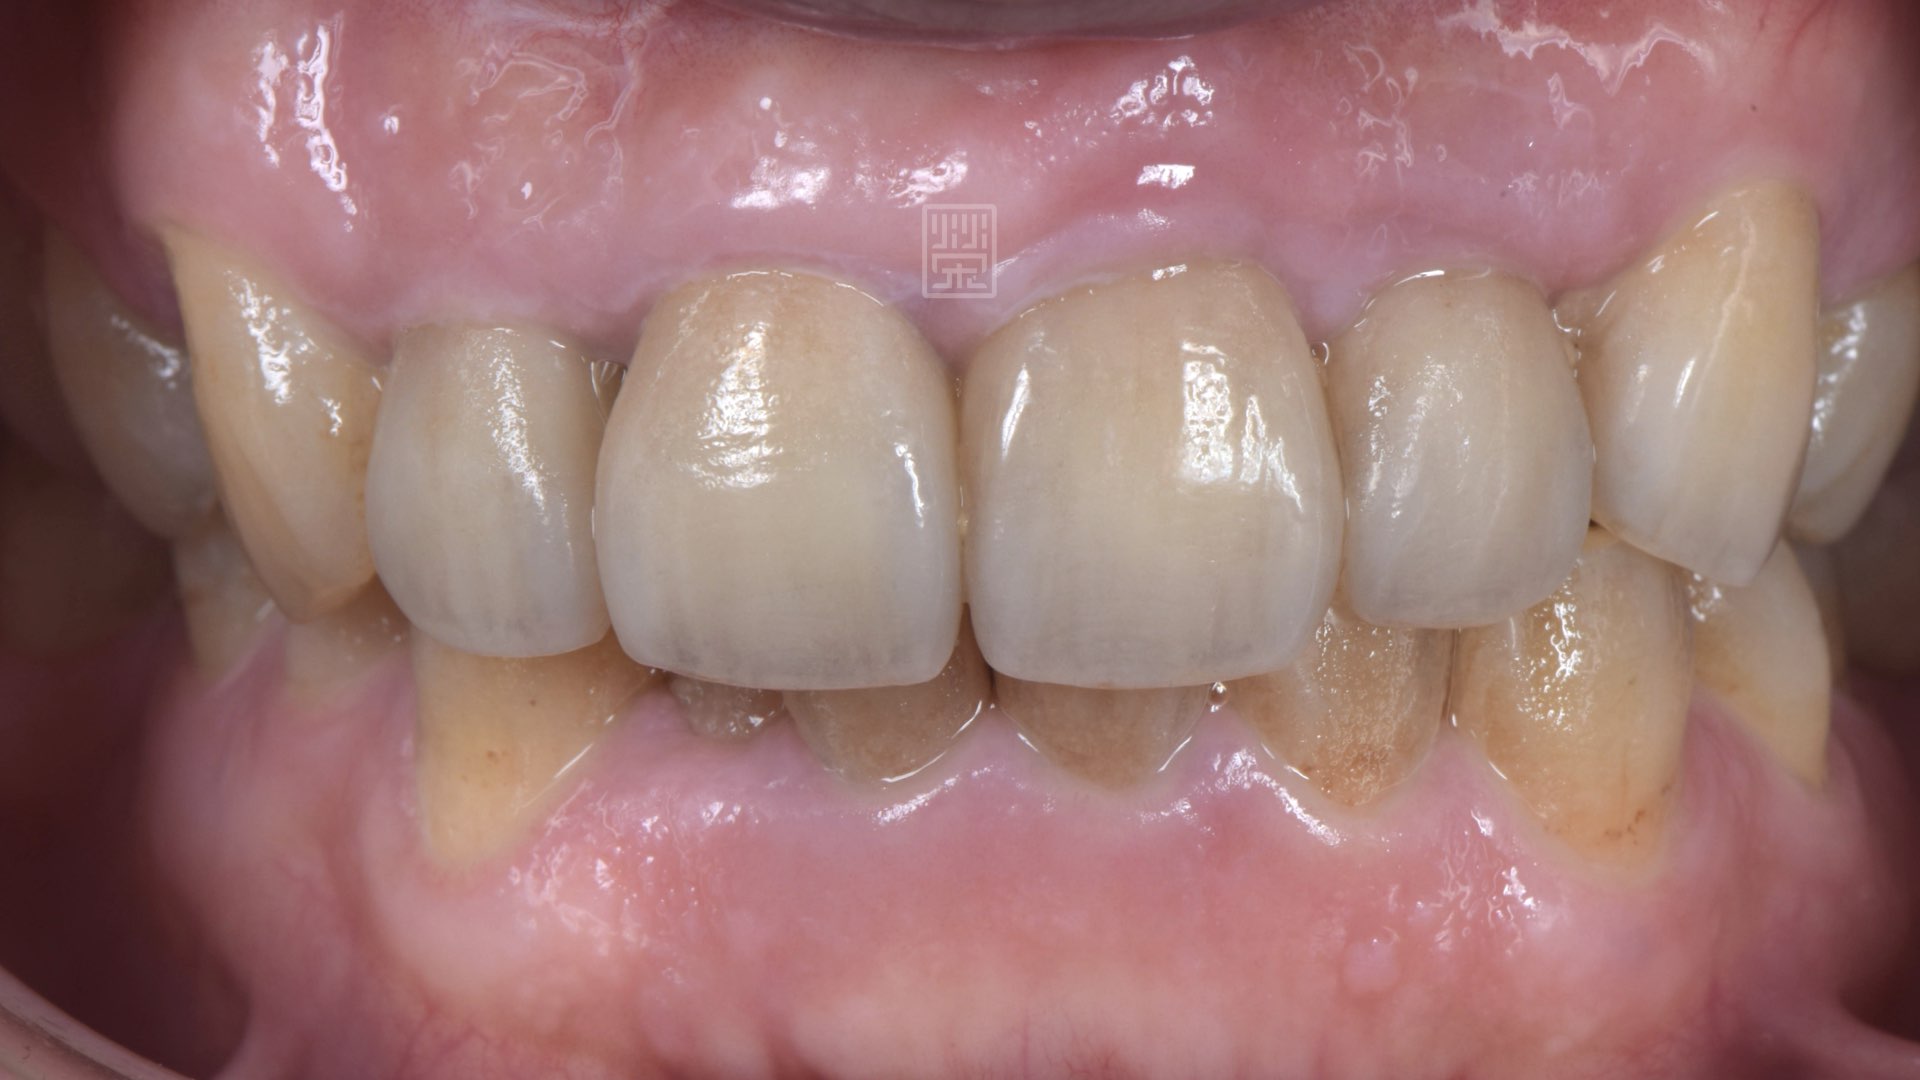

左側運動與右側運動皆有犬齒導引保護

smile~~